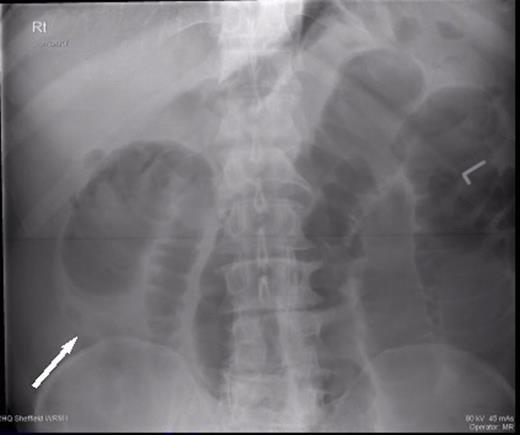

Plain radiograph showing dilated small loops of bowel with a transition point in the right upper quadrant

Two weeks later, he was readmitted with worsening pain and absolute constipation. Abdominal X-ray showed marked dilatation of the proximal and mid small bowel loops in keeping with high grade small bowel obstruction. CT confirmed this, demonstrating the classic donut sign on coronal reformat; the wall of the intussusception appeared thickened but no definite mass lesion was seen at this point.